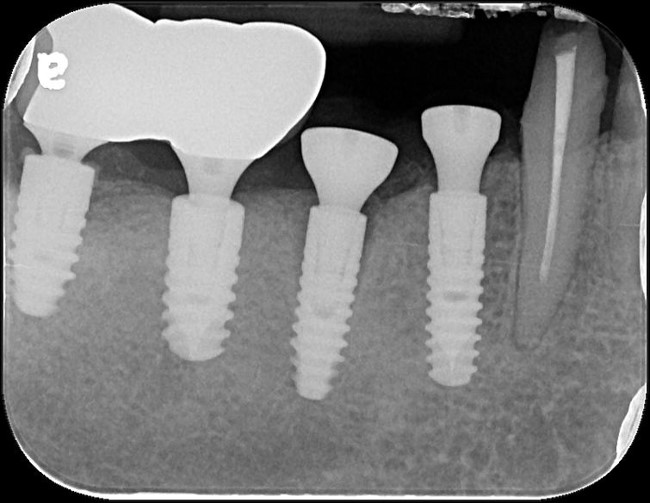

術後X光